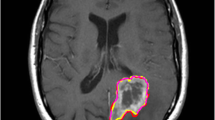

The automated segmentation of brain tumours utilizing multimodal magnetic resonance imaging (MRI) is crucial in researching and monitoring disease progression. To aid in distinguishing gliomas into intertumoural classes, efficient and precise segmentation methods are utilized to differentiate gliomas into intratumourally categorized types. Deep learning algorithms outperform classical context-based computer vision techniques in circumstances that need the segmentation of objects into categories. Convolutional neural networks (CNNs) are extensively used in medical image segmentation, and they have significantly improved the accuracy of brain tumour segmentation in the present generation. Specifically, this research introduces a residual network (ResNet), a blend of two segmentation networks that employ a primary but simple combinative method to provide better and more accurate predictions. After each model was trained on the BraTS-20 challenge data, it was analysed to yield segmentation results. Among the different methodologies examined, ResNet produced the most accurate results compared to U-Net and was thus chosen and organized in many ways to arrive at the final forecast on the validation set. The ensemble acquired dice scores of 0.80 and 0.85 for the augmentation of the tumour, total cancer, and tumour core, respectively, demonstrating more excellent performance than the present technology in use.